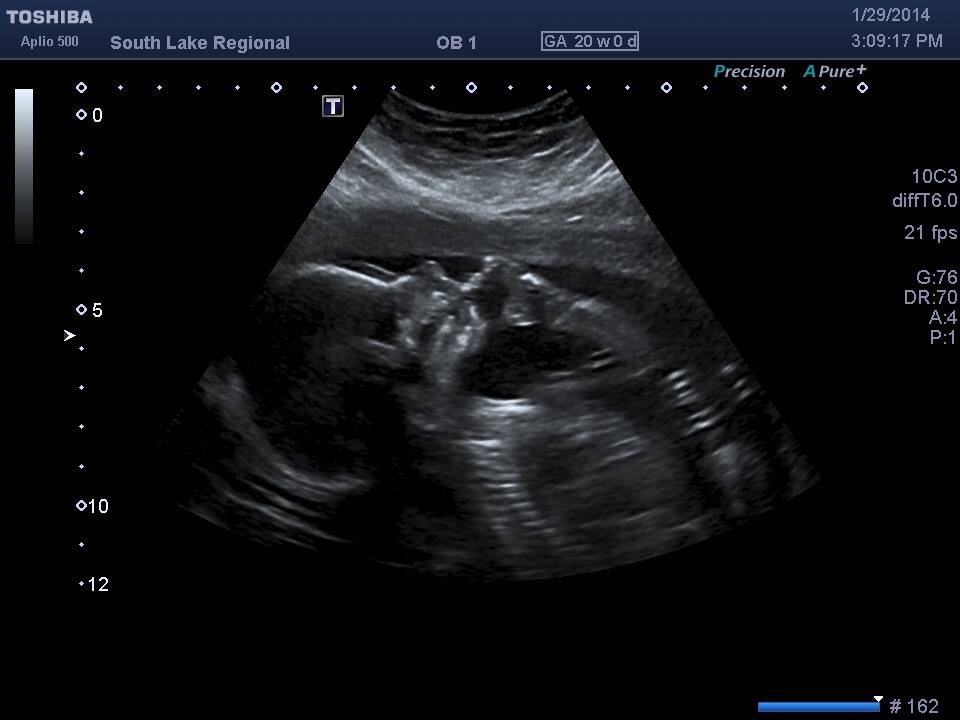

I thought to share my confirmed pics...from early on most guessed girl from skull and nub theory...hope everyone is doing fantastic :)Attachment 16855Attachment 16856Attachment 16857

She is talking in the womb, another sign of a girl :)